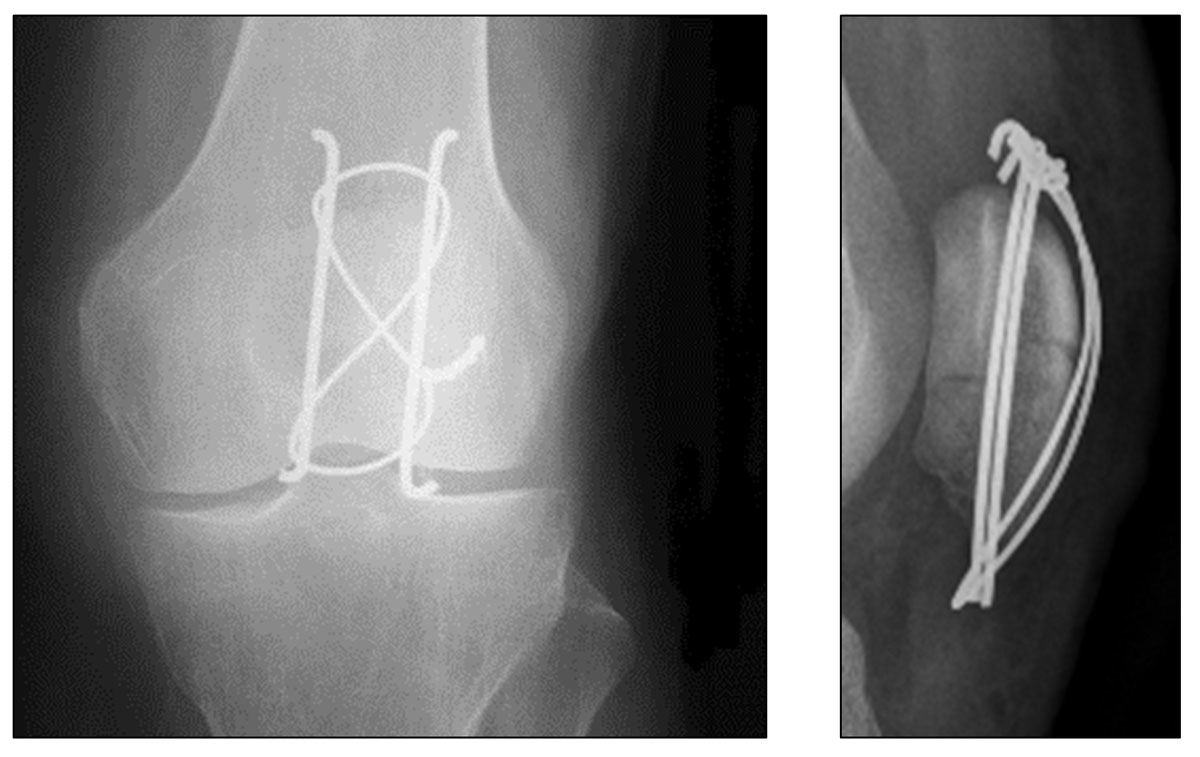

The technique developed in the 1950s by the Arbeitsgemeinschaft für Osteosynthesefragen / Association for the Study of Internal Fixation (AO/ASIF) for transverse fractures is ideal because it uses the compression of the braces during bending movements, which allows early mobilisation [13]. This technique converts the anterior tension forces produced by the extensor mechanism and knee flexion into compression forces at the articular surface (fig. 2). For maximum efficiency, there should be no loss of substance on the articular surface of the patella. Two parallel pins are inserted, then the brace is made of a metal wire that passes in front of the patella and then behind each pin by making a “figure of 8” (fig. 3). The pins are bent and depressed so as not to interfere with the soft tissues [14]. This technique gives good results in more than 80% of cases [15].

Figure 3 X-ray of a patella with tension band construct (CHUV).